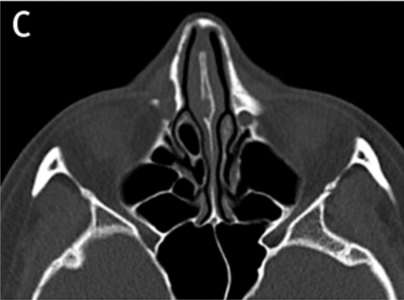

At VG Plastic Surgery, we carry out precise analysis and diagnosis procedures using 3D CT scans prior to surgery This is to analyze the problems that cannot be detected through consultation from a multi-faceted approach

An experienced plastic surgeon can determine the state of the nasal bone and the septal nasal cartilage based on a visual inspection alone. However, in order to determine the state of the nasal septum in the deeper parts, the degree of curvature of the nasal bone, the overall size and shape, and asymmetry, there is a need to perform a 3D analysis using 3D CT scans, which helps the surgeon formulate a more accurate and safer surgical plan. Of particular note, in the event of corrective nose surgery, a 3D analysis will reveal the state and notable characteristics of the implant and the septal nasal cartilage as well as the potential functional problems such as septal deviation in advance.

3D CT scans tailored to rhinoplasty procedures enable a multi-faceted analysis of the size and shape of the nasal bone, the septal nasal cartilage and the degree of curvature of the bone and/or cartilage and allow the surgeon to check for enlargement of the inferior nasal concha, presence of implants and determine the implant type and problems.